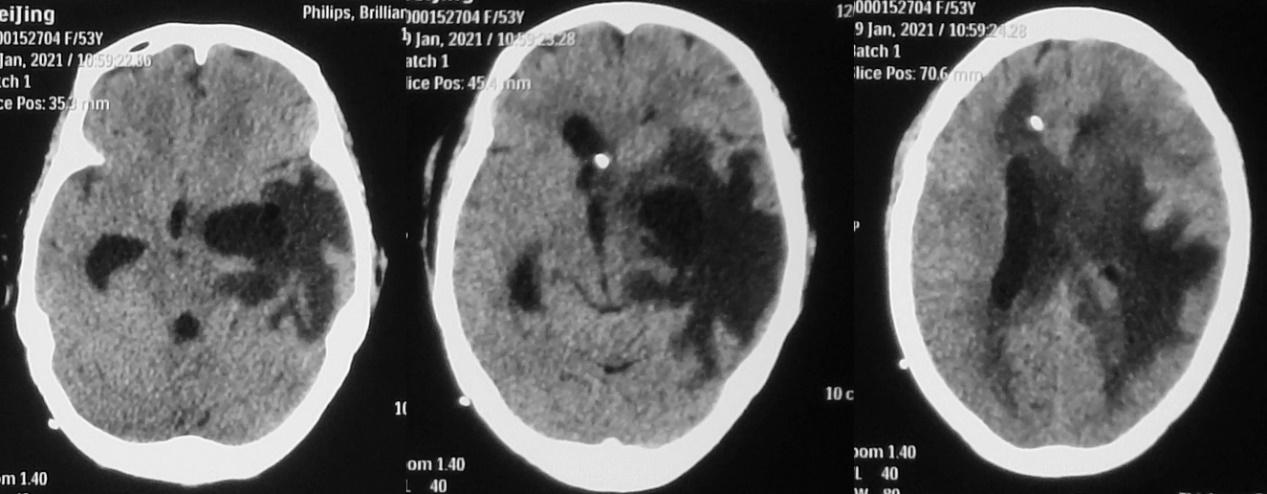

患者无发热,可遵嘱动作,于脑脓肿清除术后第29天,右侧脑室穿刺术后26天,第二次左侧颞角引流术后第6天,即2021年1月6日,夹闭右侧脑室引流管观察。

但夹闭引流管后2天,即2021年1月8日,患者意识变差,呈模糊状态,不能遵嘱动作,复查头颅CT见右侧脑室扩张( 图-22 ),于是开放右侧脑室引流管继续引流。

图-22: 2021年1月8日头CT

此后患者神志清楚,可遵嘱动作,无发热。于发病后65天,即脑脓肿清除术后第36天,右侧脑室穿刺术后33天,第二次左侧颞角引流术后第13天,即2021年1月13日,行右侧脑室腹腔分流术。

脑室腹腔分流术后第1天,即2021年1月14日,患者神志清楚,复查头颅CT见右侧脑室稍扩张,左侧脑室颞角仍可见保留的外引流管( 图-23 )。

图-23: 2021年1月14日头CT

但脑室腹腔分流术后第4天,即2021年1月17日,患者出现发热,体温38.1℃,复查头颅CT呈术后改变( 图-24 ),给予万古霉素抗炎治疗。

图-24: 2021年1月17日头CT

于脑脓肿清除术后第41天,第二次左脑室颞角引流术后第18天,脑室腹腔分流术后第5天,即2021年1月18日,拔除左侧脑室颞角外引流管。

脑室腹腔分流术后第6天,拔除左侧脑室颞角外引流管后1天,即2021年1月19日患者发热好转,病情平稳。复查头颅CT见左侧脑室颞角较前稍扩张( 图-25 );继续观察。

图-25: 2021年1月19日头CT

但发病后77天,即脑脓肿清除术后第48天,脑室腹腔分流术后第12天,即2021年1月25日,患者出现精神变差,同时呕吐1次。复查头颅CT较前(2021年1月19日)无明显变化( 图-26 )。

图-26: 2021年1月25日头CT

次日,即2021年1月26日,患者精神仍差,反应迟钝,呕吐2次。复查头颅CT见左侧脑室颞角稍扩张( 图-27 )。

图-27: 2021年1月26日头CT

当天,即发病后78天,即脑脓肿清除术后第49天,脑室腹腔分流术后第13天,即2021年1月26日,行第3次左侧颞角外引流术。但术后患者意识无明显改善。2021年1月28日患者再次出现发热,体温38.4℃,反应迟钝,复查头颅CT见左侧脑室颞角缩小,但右侧脑室较前扩张( 图-28 )。第3次左侧脑室颞角引流后脑脊液细菌培养回报为表皮葡萄球菌。给予抗炎治疗。

图-28: 2021年1月28日头CT